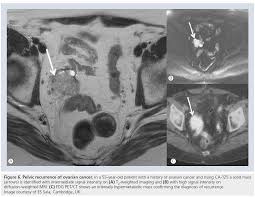

Certain symptoms, such as bloating and pelvic pain, are commonly caused by a number of conditions. Many people with early ovarian cancer have no signs or symptoms of the condition. Department of health and human services office on. Ct scans also are used to monitor disease recurrence. It may have spread within the pelvis or abdomen, or further away to other parts of the body such as the lungs.